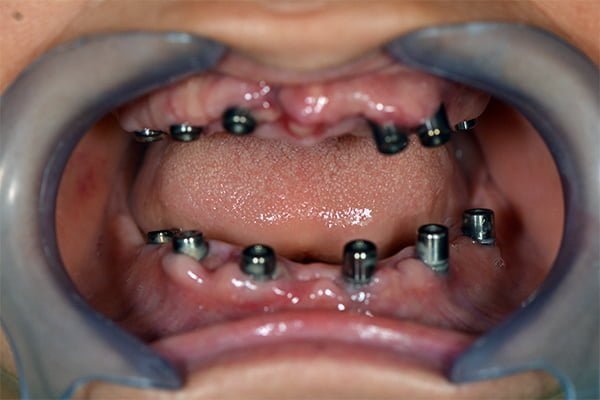

L’ostéointégration désigne la connexion directe, structurelle et fonctionnelle entre l’os vivant et la surface d’un implant dentaire en titane ou en zircone. Cette intégration se caractérise par l’absence de tissu conjonctif fibreux entre l’implant et l’os, assurant ainsi une stabilité à long terme. L’ostéointégration est cruciale pour le succès des implants dentaires, car elle garantit que l’implant supportera les forces masticatoires sans se détacher ou provoquer des douleurs.

Les implants dentaires sont principalement fabriqués à partir de titane et de ses alliages, en raison de leurs propriétés biocompatibles exceptionnelles. Le titane est non seulement résistant et léger, mais il possède également une capacité unique à se lier directement à l’os sans provoquer de réaction immunitaire ou de rejet. Des recherches récentes explorent également l’utilisation de céramiques, telles que l’oxyde de zirconium, qui offrent une alternative esthétique et biocompatible au titane. La surface de l’implant joue un rôle crucial dans l’ostéointégration. Les surfaces rugueuses, obtenues par des traitements physiques ou chimiques, augmentent la surface de contact avec l’os, favorisant ainsi une intégration plus rapide et plus solide.

La composition chimique et la rugosité de la surface de l’implant jouent un rôle crucial dans l’ostéointégration. Des surfaces rugueuses favorisent une meilleure adhésion cellulaire et une prolifération accrue des ostéoblastes. Les traitements de surface, tels que l’anodisation, le sablage et l’acidification, augmentent la rugosité et améliorent la bioactivité de l’implant.

Les techniques chirurgicales jouent également un rôle crucial. Une manipulation atraumatique de l’os, minimisant les dommages et la nécrose osseuse, est essentielle pour favoriser une ostéointégration rapide et efficace. L’utilisation de guides chirurgicaux et de techniques de forage précises permet d’assurer une insertion optimale de l’implant.